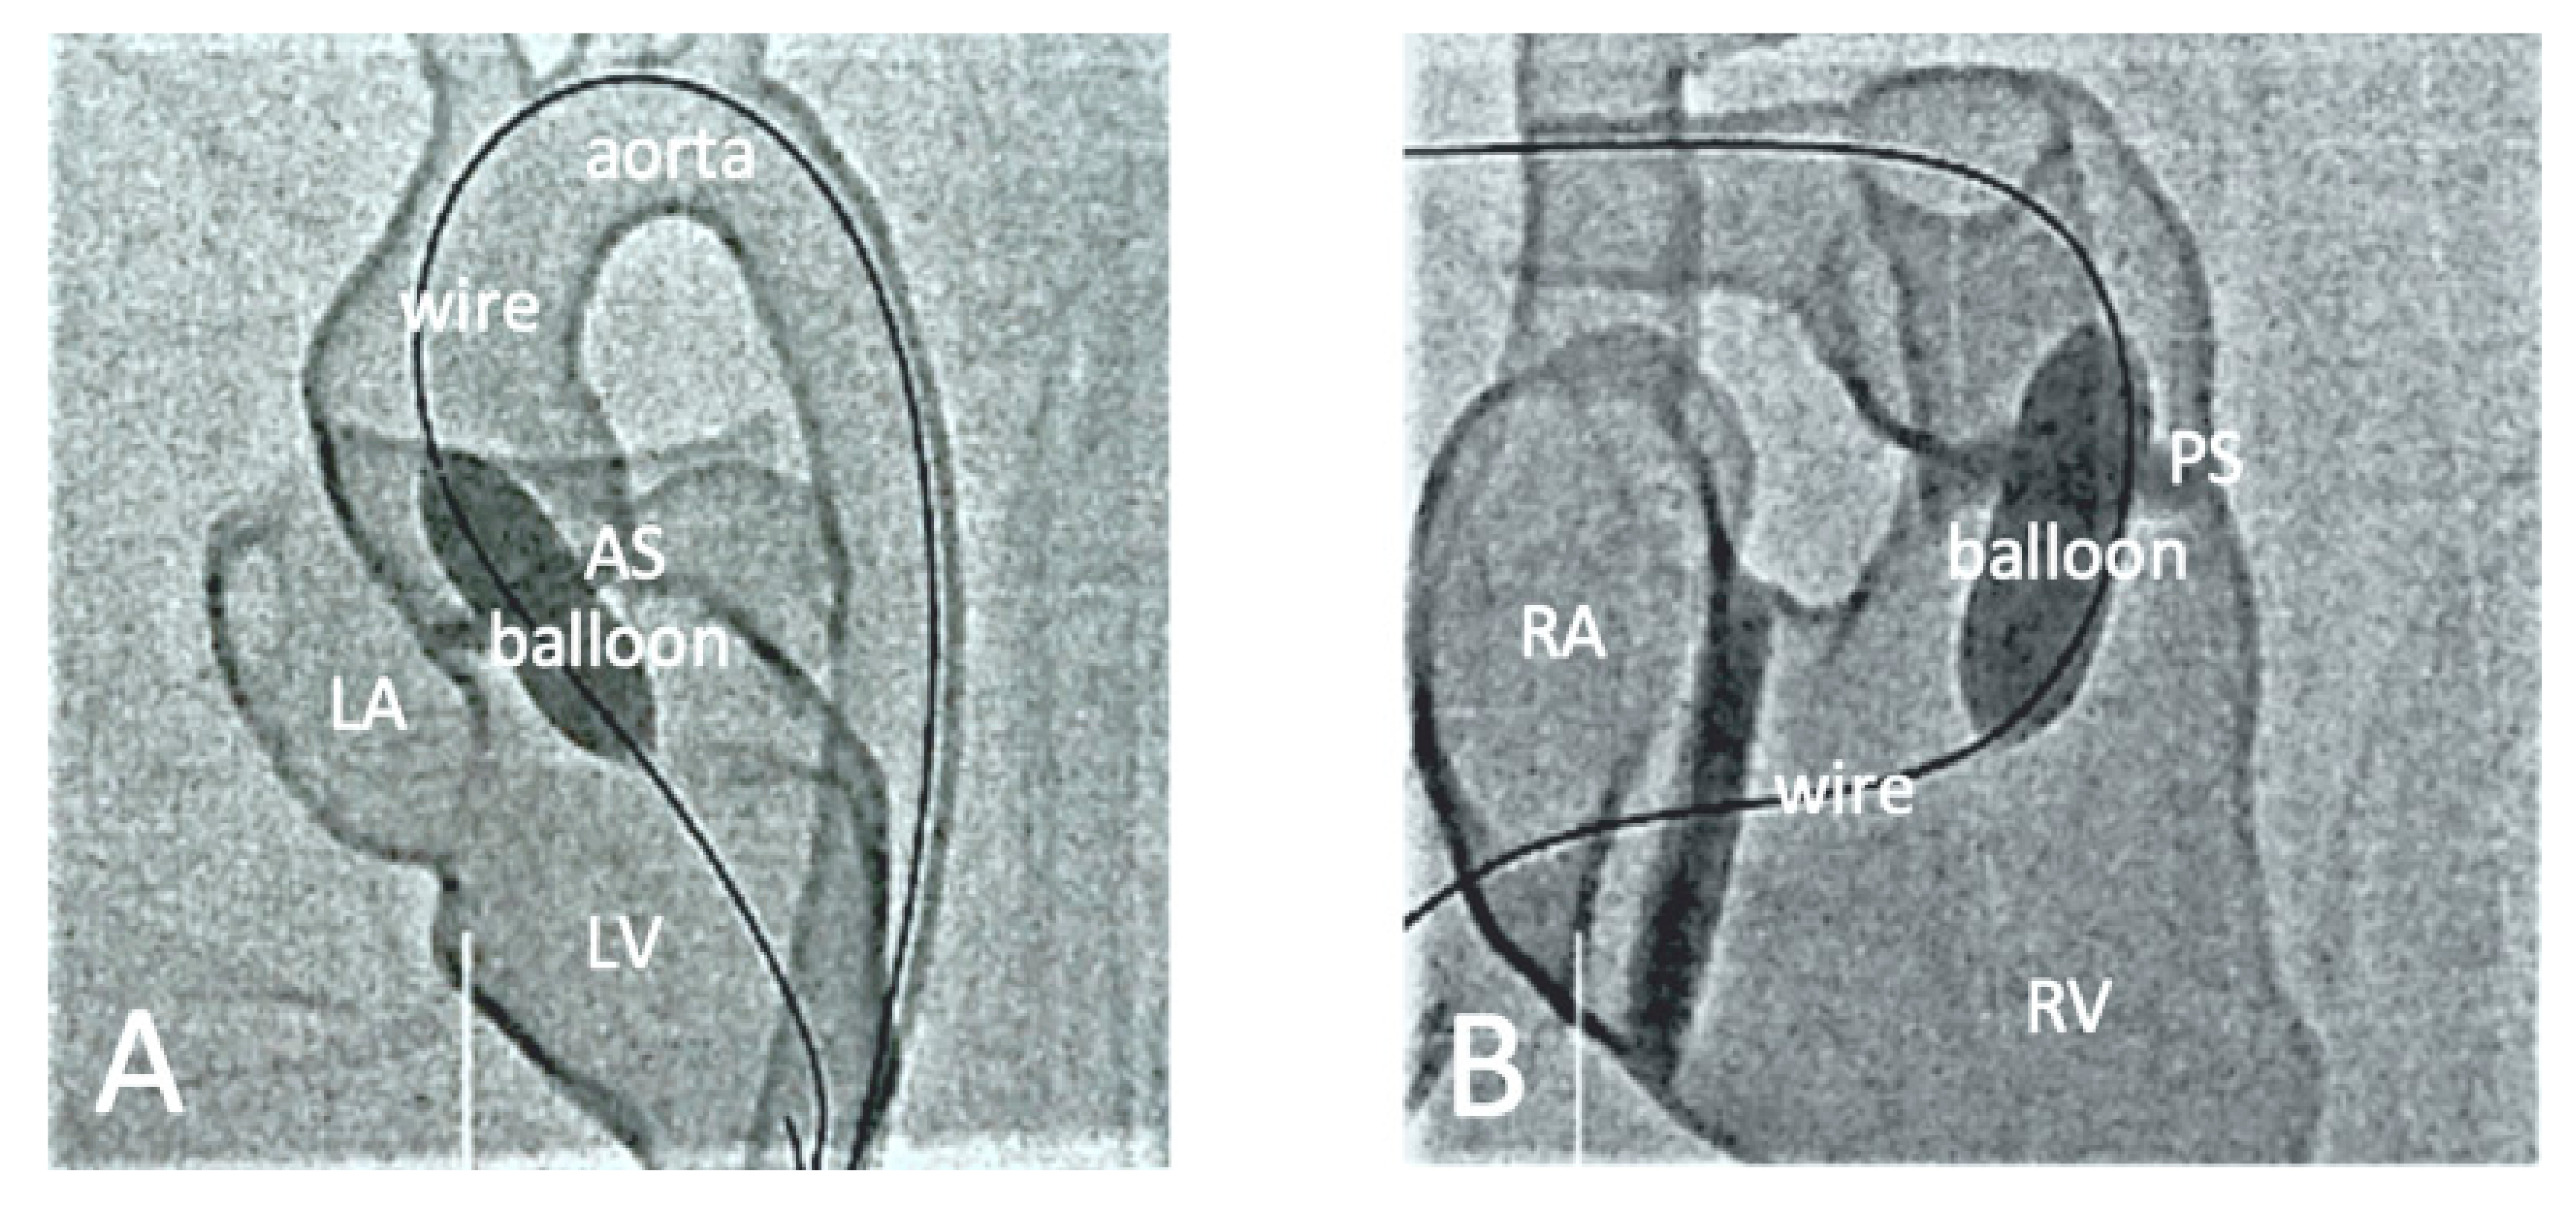

4.5. The Use of 3D-Printed Devices in Treating Cardiovascular Disease